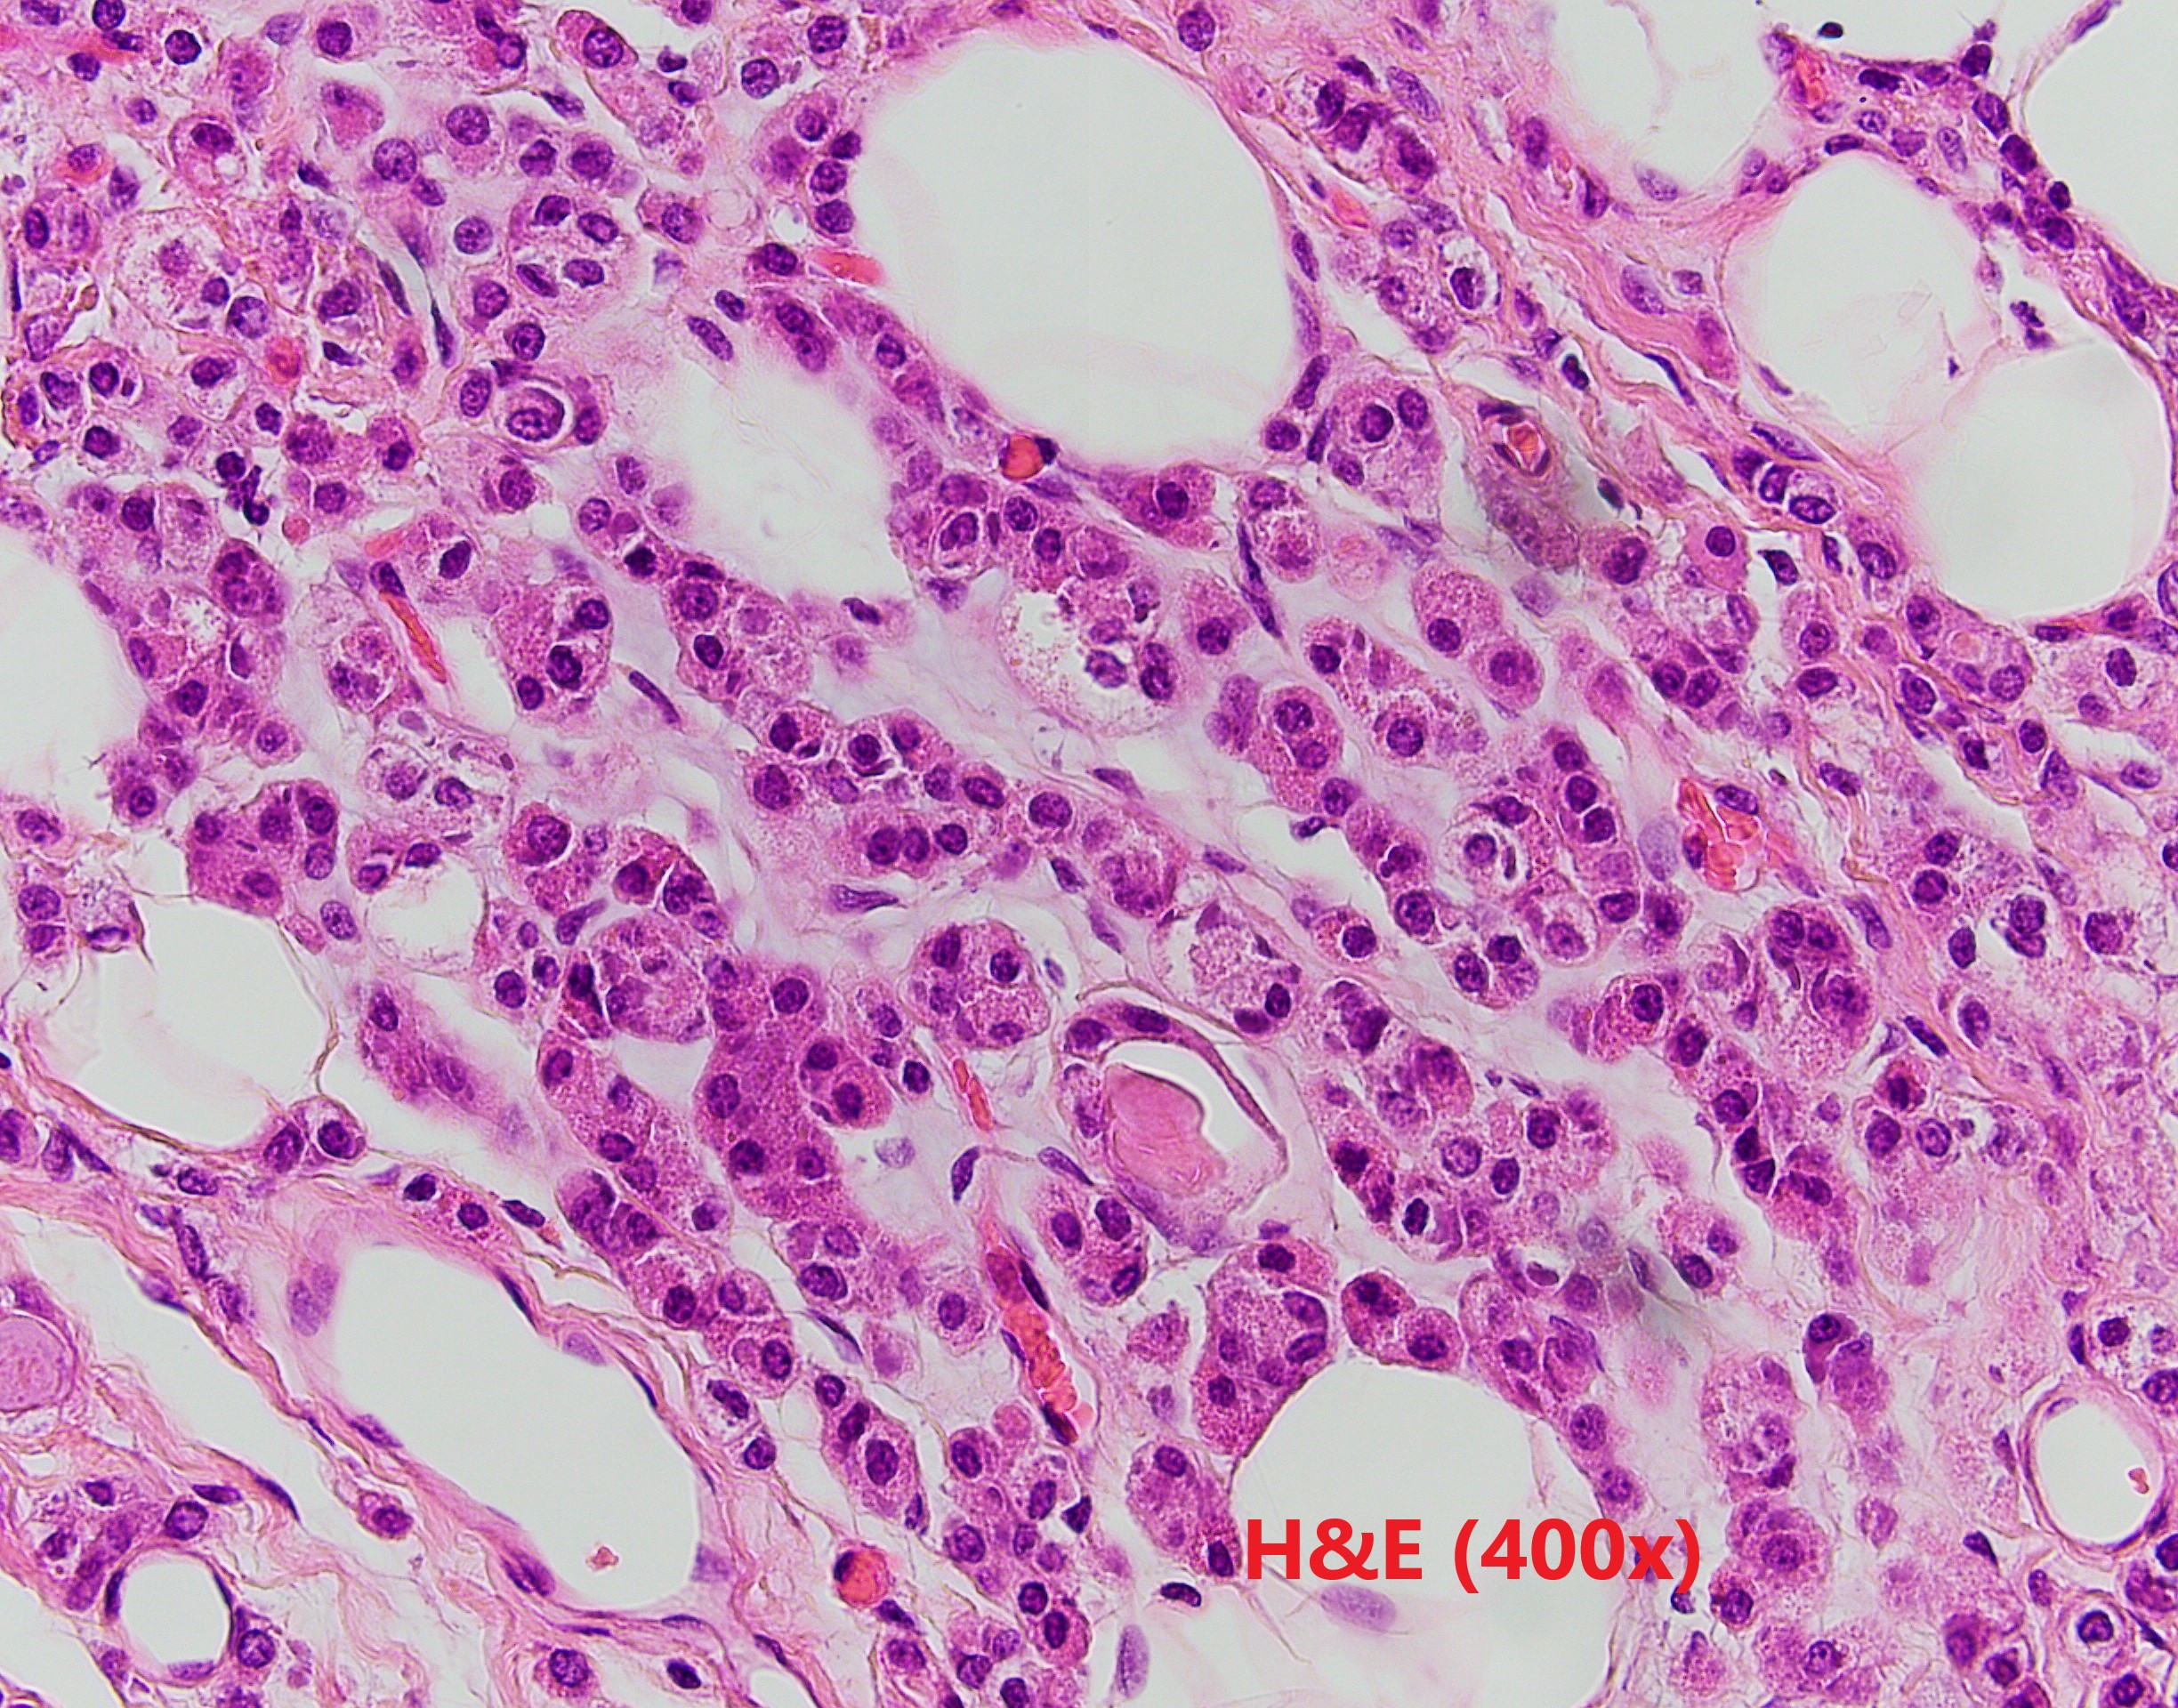

The patient is a middle-aged female with an irregular enhancing mass in the right breast. After resection, IHC revealed GATA3 and CK7 positivity and p63 negativity. Further studies of lysozyme and a1-antichymotrypsin are shown.

Breast acinic cell carcinoma (ACC) is a rare entity and usually affects women aged 20-80 years. Architectural patterns of ACC are variable, ranging from microglandular proliferation to solid. Diagnosis of ACC is mainly based on cytological features. The tumor cells show abundant eosinophilic to clear cytoplasm with coarse granules. The nuclei are usually centrally located with prominent nucleoli. Cytological atypia and mitosis can be seen. The tumor cells are usually triple negative, and positive for S100, EMA, lysozyme and α1-antichymotrypsin. The differential diagnosis is broad depends on cytomorphology. The prognosis of ACC is still unclear because the limited number of cases reported. Most of the reported patient had chemoradiation and surgery.